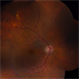

- idiopathic sclerochoroidal calcification

- Kristin Konecki, OcuSight Eye Care Center, Rochester, NY

- Fundus camera